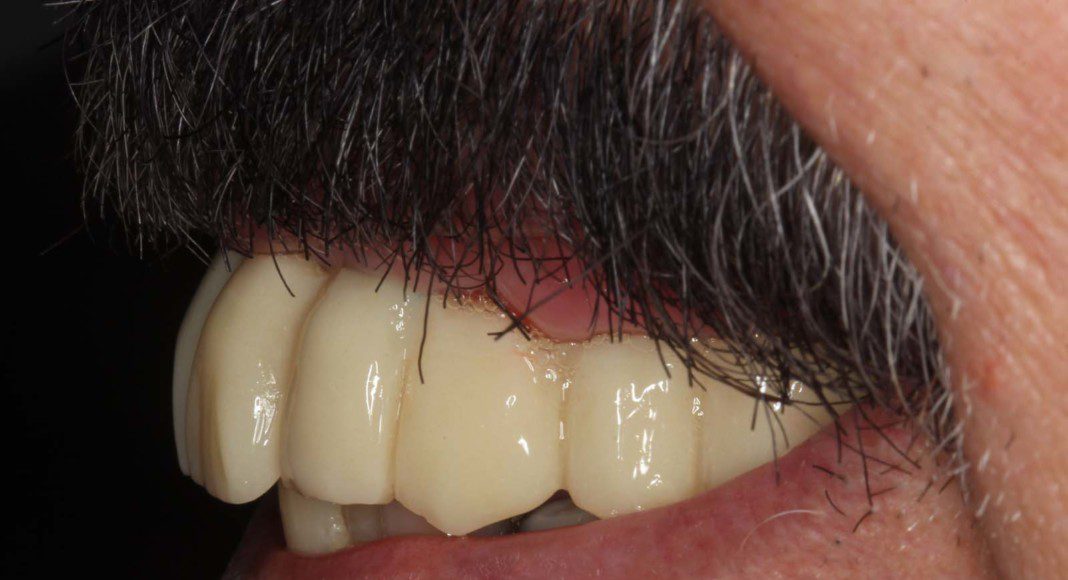

Day of surgery placement of the immediate, fixed temporary bridge on all implants. Not the convex contours to which the tissues can heal, ideally.